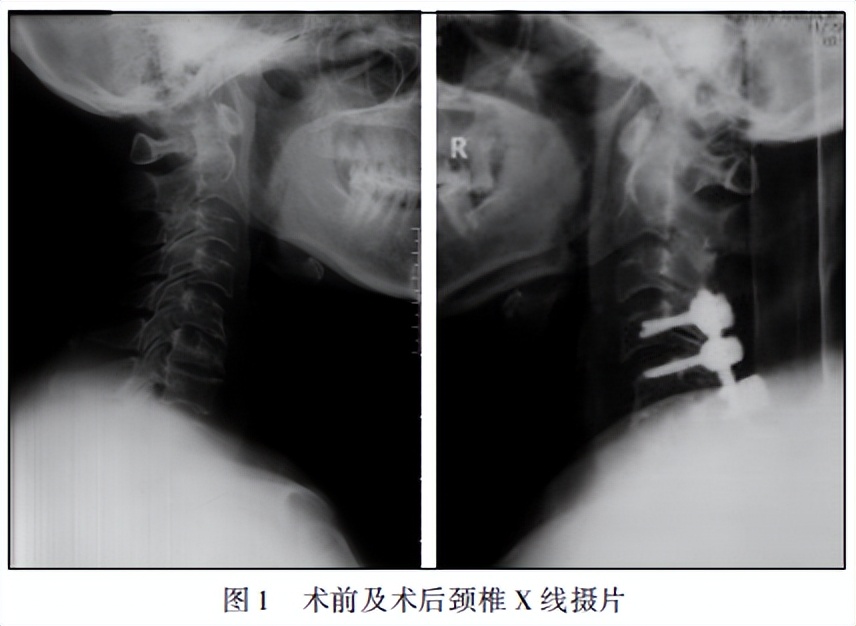

2012 年 10 月出现颈肩部疼痛,伴有胸锁关节处疼痛,偶有髋关节、膝关节及骶髂关节疼痛,当地医院行颈椎 X 线摄片(图 1)提示 C6骨质破坏;MRI(图 2)提示 C6椎体呈长 T1 、稍长 T2异常信号,脂肪抑制序列高信号不被抑制;全身骨扫描(图 3)提示双侧胸锁关节、颈椎、第 5 胸椎、左侧骶髂关节可见放射性摄取增高灶;考虑“多发性骨转移瘤表现”。因担心高位截瘫的风险,于 2012 年 11 月 27 日在全麻下颈椎后路椎板减压扩大成形术(单开门),内固定术,微波灭活术。术后颈肩部疼痛无明显改善,并出现右肩关节活动受限。